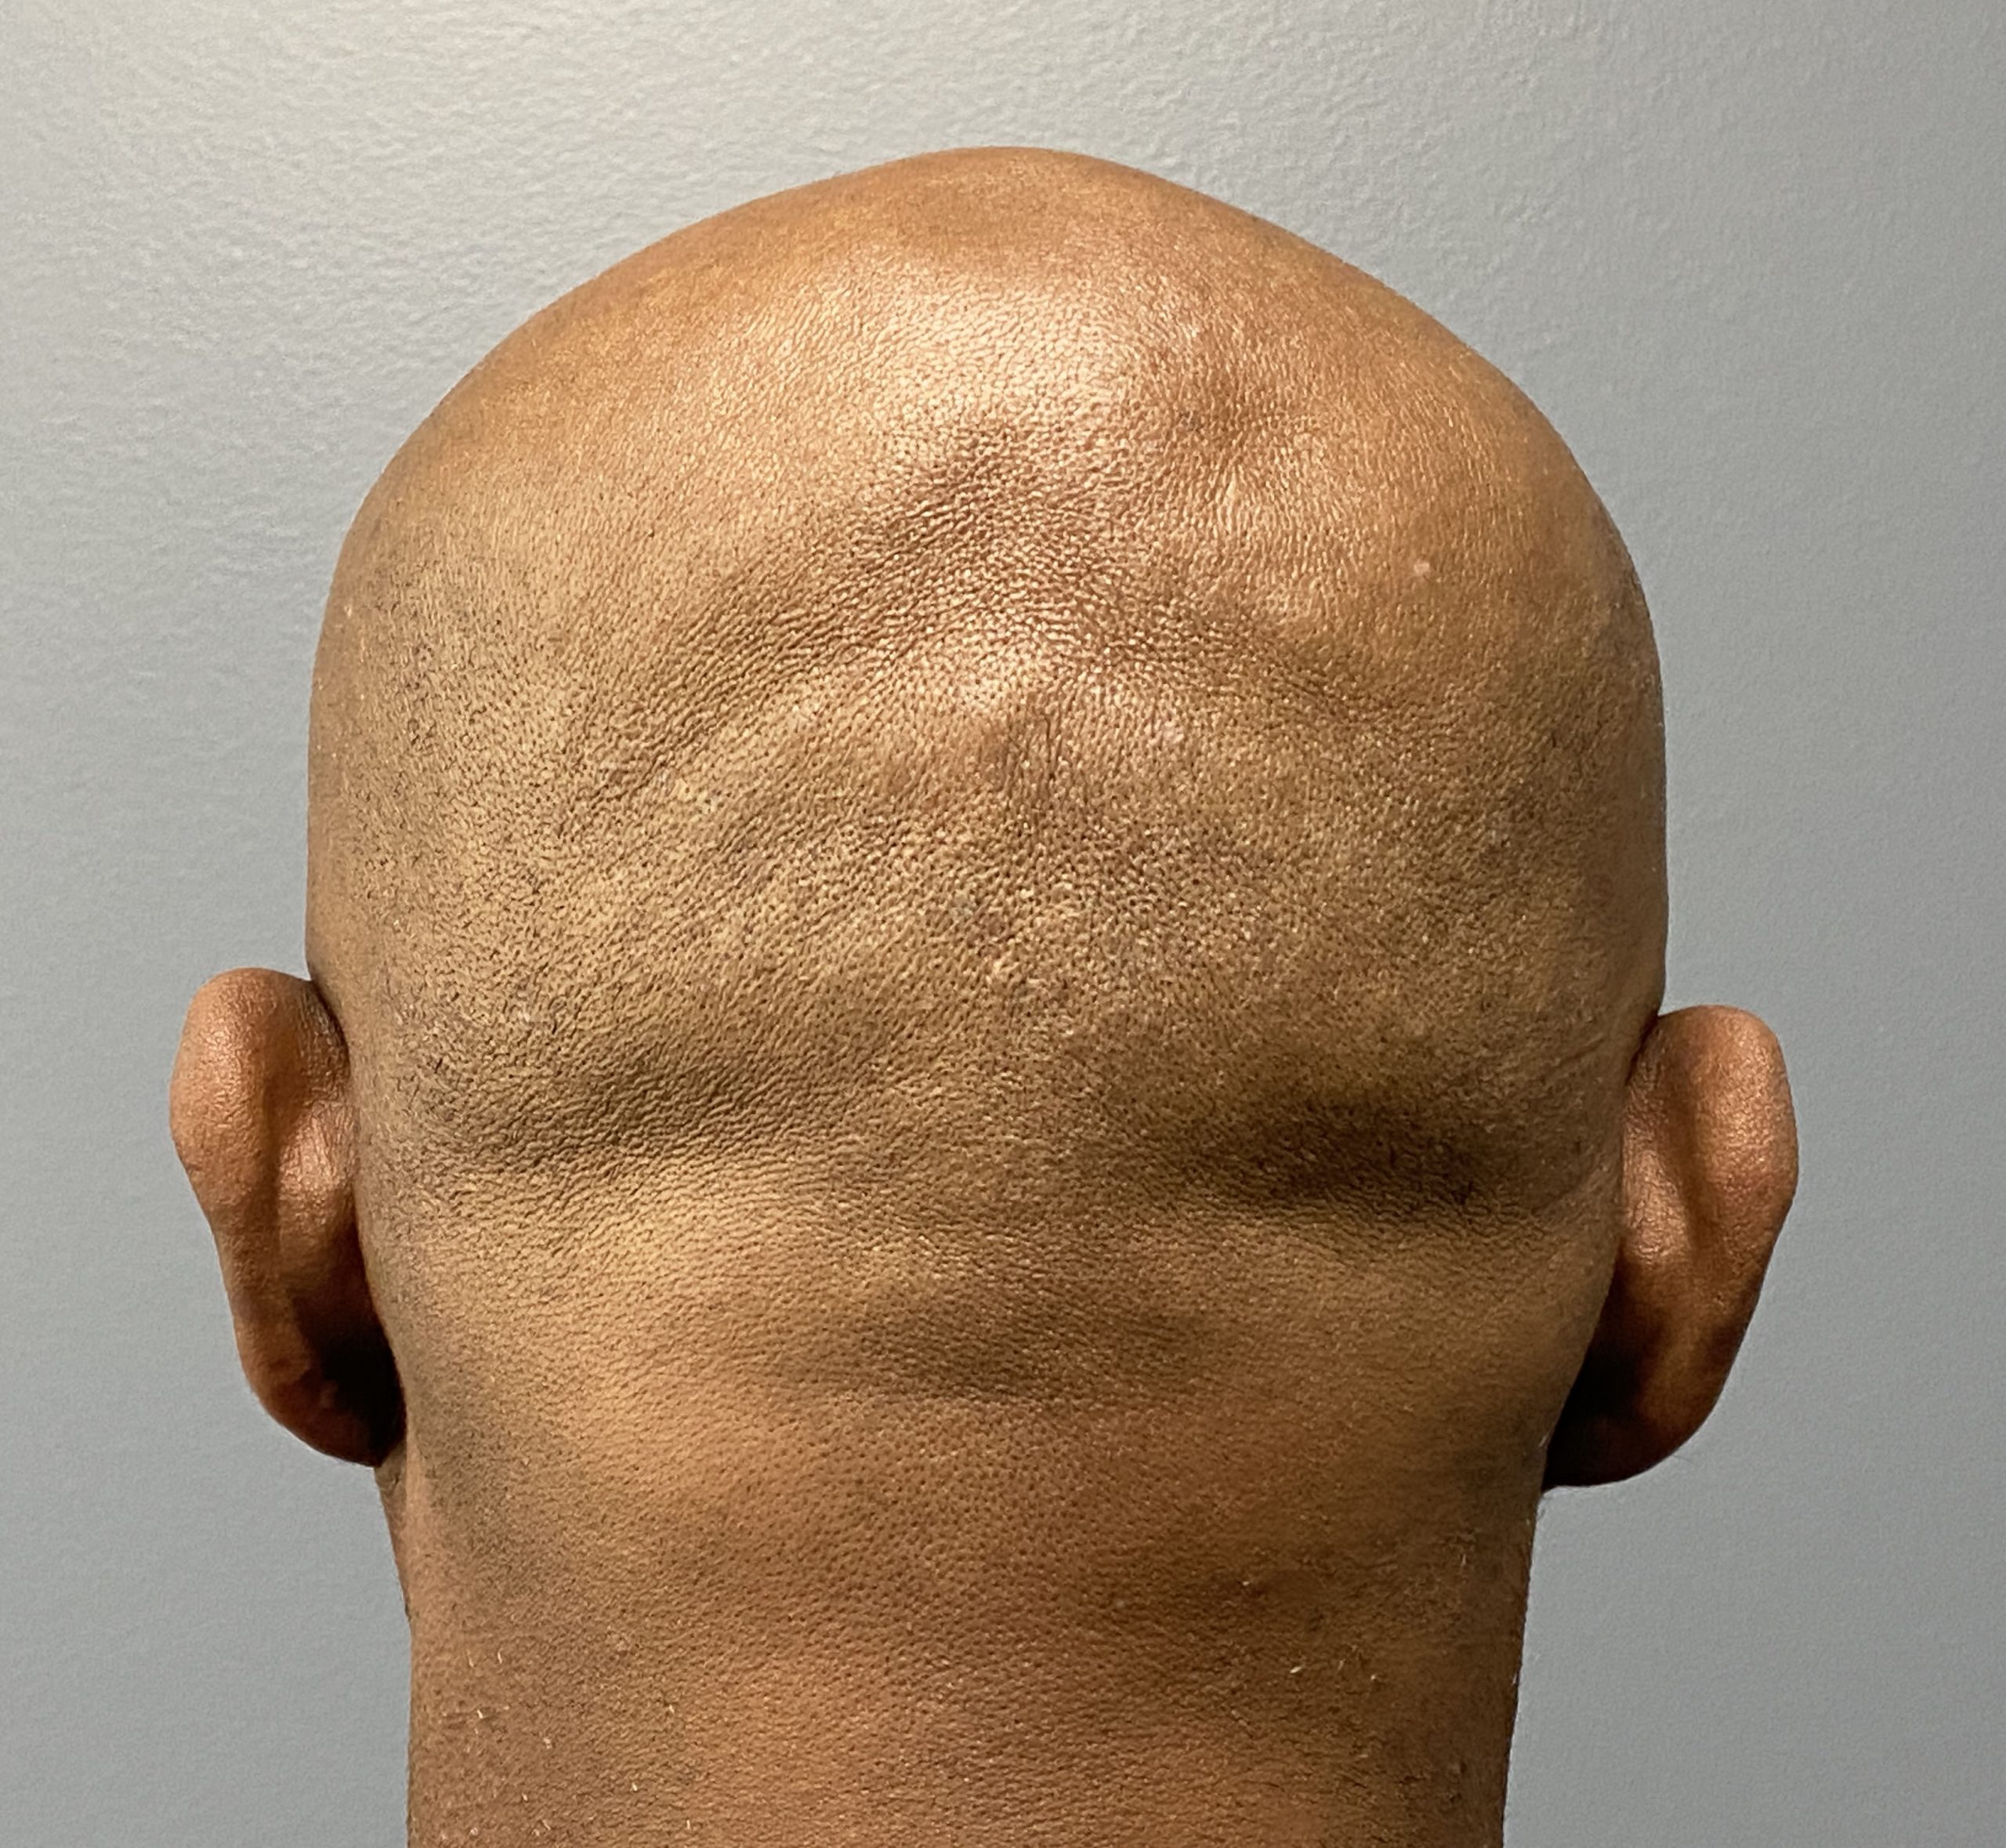

Patient 129

Desire for reduced width/convexity on the sides of his head.

Head narrowing using a temporal muscle transposition technique seen one day postop. He also had an concurrent occipital skull reduction done hence the tape over his incision.

Desire for reduced width/convexity on the sides of his head.

Head narrowing using a temporal muscle transposition technique seen one day postop. He also had an concurrent occipital skull reduction done hence the tape over his incision.